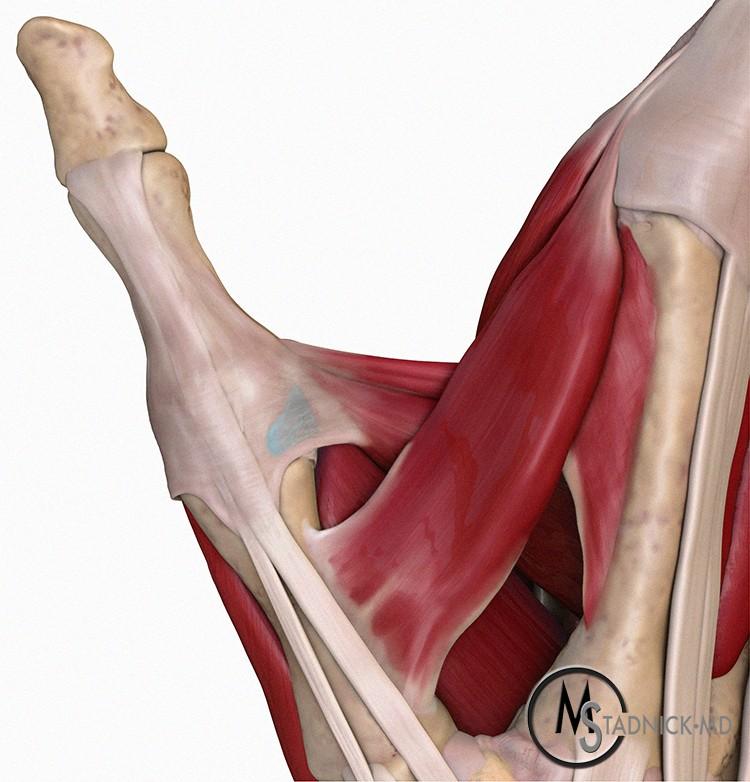

The Stener lesion, first described by Bertil Stener, 2 occurs when the torn UCL becomes proximally retracted during radial deviation of the joint and the adductor aponeurosis becomes interposed between the joint and the torn retracted ligamentous fibers (Figure 3). The interposed tissue from the adductor aponeurosis prevents the torn end of the UCL from approximating to its insertion point on the proximal phalanx base, and thus healing with conservative therapy such as casting becomes impossible. 3 A Stener lesion is thus felt to be an absolute indication for surgical repair of the UCL.

Figure 3: (3A) Dorsal Illustration of the normal thumb MP joint showing the intact UCL (in blue) deep to the fibers of the adductor aponeurosis. (3B) With a Stener lesion, the torn stump of the UCL is retracted proximal to the leading edge of the aponeurosis, which becomes interposed between the torn ligament and its anatomic insertion site.